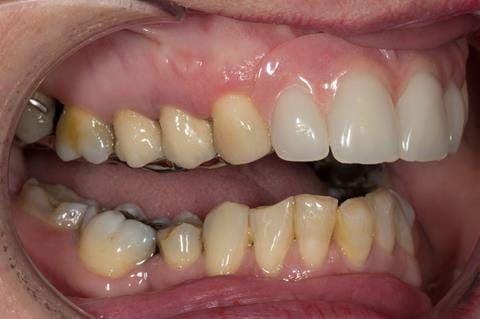

- UR2 peri-radicular periodontitis with a peri-radicular area on the root apex. Retrograde amalgam filling from a previous apicectomy. No visible root canal or root canal filling. Large circumferential marginal gap between the crown and tooth. Large post and core present. Very little tooth structure remaining resulting in a fragile tooth with increased potential for fracture.

- UR1 peri-radicular periodontitis with a small peri-radicular area on the root apex with wide blunderbuss apex. Radio-opaque root canal filling present approximately 3 mm short of the radiographic apex. Large circumferential marginal gap between the crown and tooth. Large post and core present. Very little tooth structure remaining resulting in a fragile tooth with increased potential for fracture.

- UL1 peri-radicular periodontitis with a peri-radicular area on the root apex. Retrograde amalgam filling from a previous apicectomy. Visible root canal space with no sign of root canal filling. Large circumferential marginal gap between the crown and tooth. Large post and core present. Very little tooth structure remaining resulting in a fragile tooth with increased potential for fracture.

- UL2 peri-radicular periodontitis with a peri-radicular area on the root apex. No visible root canal or root canal filling. Large circumferential marginal gap between the crown and tooth. Large post and core present. Very little tooth structure remaining resulting in a fragile tooth with increased potential for fracture.

- High smile line showing gum above gingival zeniths of upper front teeth when smiling. Aesthetic failure of the upper four incisors with inflammation of the gingivae and mis-match of the gingival zenith levels.

- Other than the maxillary incisors the remaining dentition was in marginally better condition being moderately to heavily restored. Many will probably require replacement and restoration from time to time mainly from wear and tear owing to occlusal forces.